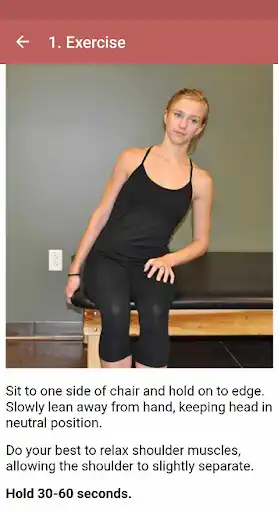

Rotator cuff tears can be caused by sudden and backward movement of the shoulder, excessive strain of the shoulder, and falling. Symptoms are usually shoulder pain, a clicking sound from the shoulder while moving the arm, and limitation of movement and muscle weakness.

After the examination, the patient is directed to surgical or other shoulder treatment methods according to the degree of the tear. Exercise therapy is recommended for less severe tears.

In our mobile application, exercises to help treat rotator cuff rupture are shown. When you repeat these movements regularly, shoulder pain decreases, range of motion increases and shoulder muscles become stronger.